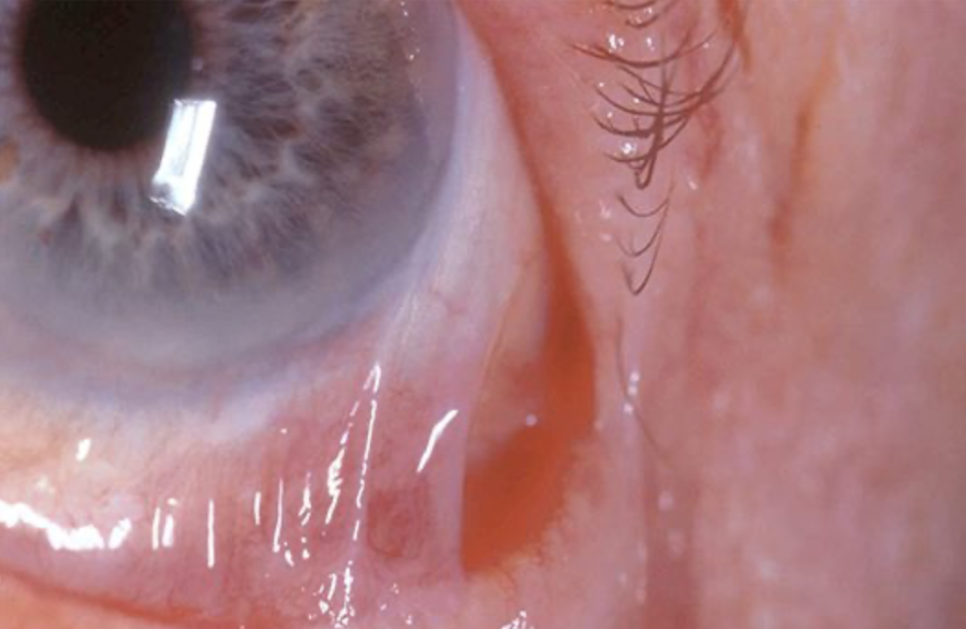

안구 이상반응 기본적으로 베타차단제의 부작용으로는 눈물막에 영향을 미쳐 건상안(안구건조)을 유발하거나 작열감이나 결막충혈 등을 일으킬 수 있습니다. 또한 반흔 유선포창(OCP)이라는 안구의 만성 염증을 일으킬 수 있습니다. 하지만 티모롤 제제는 이러한 부작용이 적은 비교적 안전한 약이기 때문에 고전압 녹내장에서 주로 사용됩니다.

반흔 유천포창 (출전.https://blog.naver.com/llkth93125/222357353441)